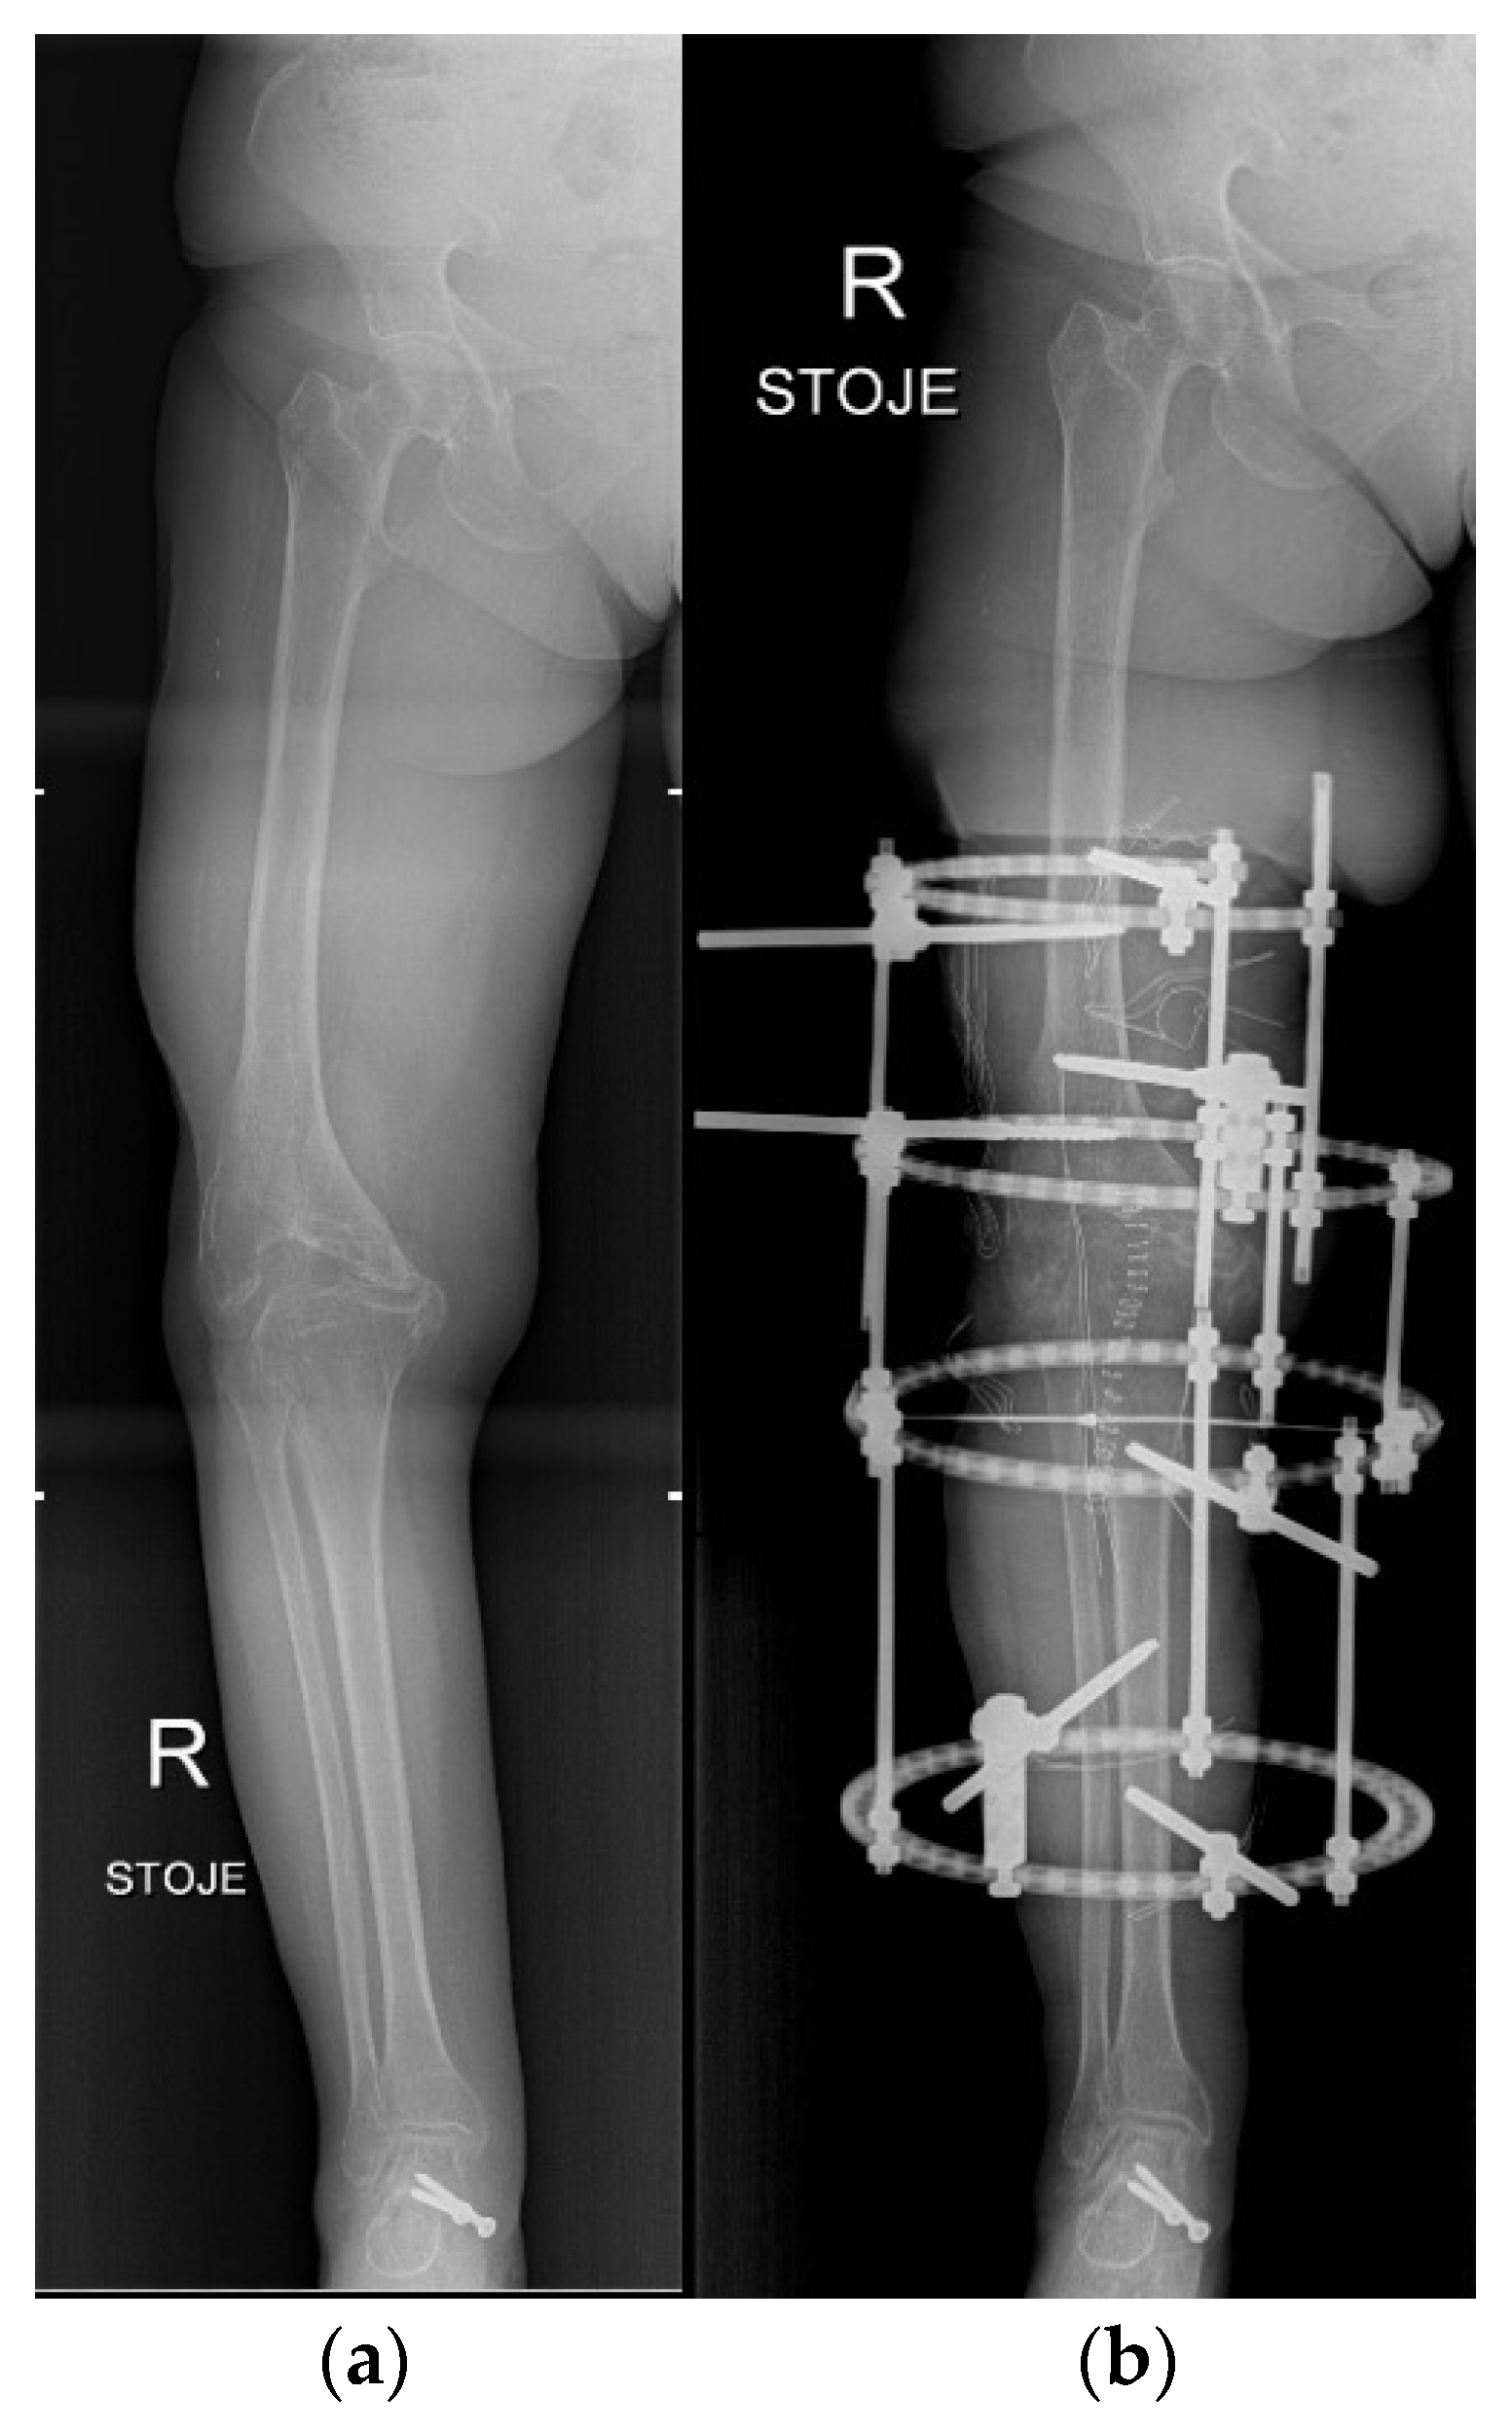

3.6. Knee

4.6. Knee

- Brumat, P.; Mihalič, R.; Kovač, S.; Trebše, R. Acute Femoral Lengthening in Adults Using Step-Cut Osteotomy, Traction Table, and Proximal Femoral Locking Plate Fixation: Surgical Technique and Report of Three Cases. Indian J. Orthop. 2022, 56, 559–565. [Google Scholar] [CrossRef]

- Waszczykowski, M.; Niedzielski, K.; Radek, M.; Fabis, J. Arthroscopic-Assisted Arthrodesis of the Knee Joint With the Ilizarov Technique: A Case Report and Literature Review. Medicine 2016, 95, e2540. [Google Scholar] [CrossRef] [PubMed]